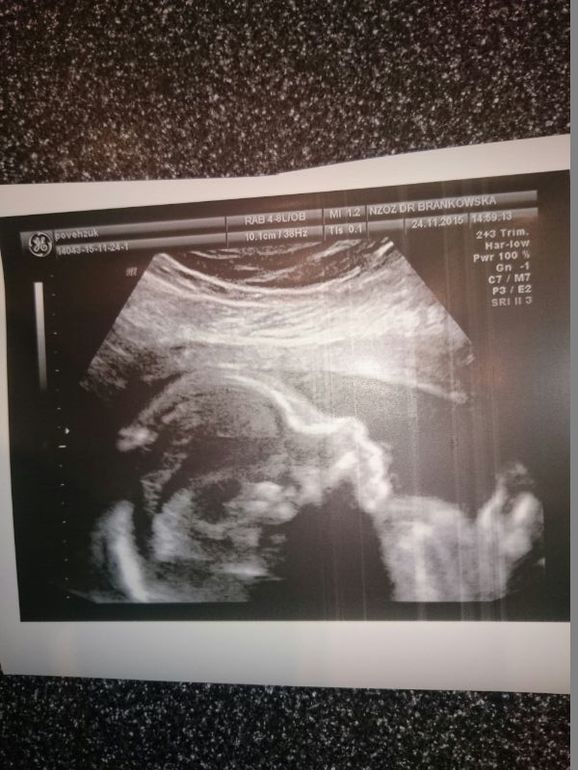

Теперь фотографии

Ноженька